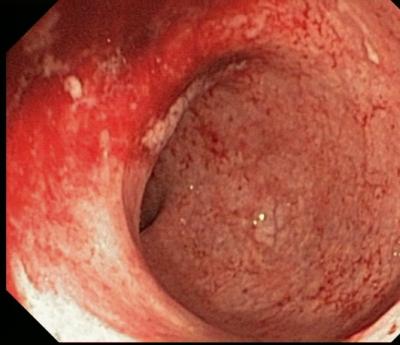

С диагностической целью при колитах показана ректороманоскопия, гдеопределяется гиперемия и отек слизистой дистальных отделов толстой кишки, на стенках кишки видно большое количество слизи, а в более тяжелых случаях - гноя; нередко находят эрозии, изъязвления и кровоизлияния.